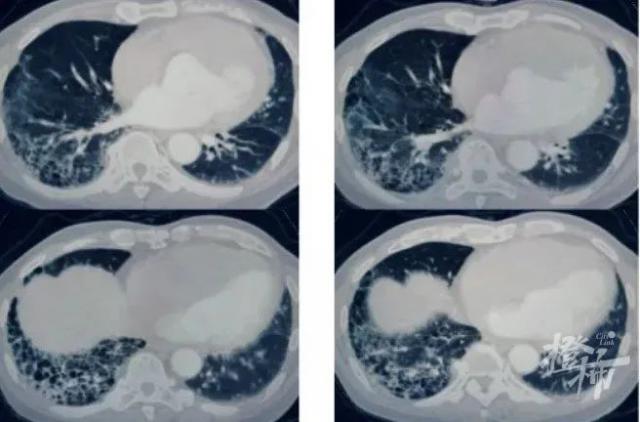

沈凌医生立即为病人安排了肺部 CT 检查,在查看图像资料时,他惊讶地发现,王大伯的肺部已经出现了明显的肺纤维化特征,更严重的是,局部已形成蜂窝状病变形态。

简单来说,肺纤维化就是正常的肺泡逐渐被纤维物质所取代,导致肺组织变硬变厚,导致正常的肺组织结构发生变化。肺部交换氧气进入血液的能力逐渐丧失,患者呼吸困难,缺氧、酸中毒、劳动力丧失,严重者可死亡。

沈凌形容道,如果把肺比作海绵,纤维化的肺就像海绵里的胶水,随着胶水的凝结而变硬。显然,如果不及时诊断和治疗,王叔叔的生命将受到严重威胁。

并且,他长期保持右侧卧位睡眠,为胃酸误吸入右下肺创造了有利条件,促使少量胃酸像涓涓细流一样在睡眠过程中反复进入右下肺。随着时间的推移,最终导致严重的肺纤维化病变。